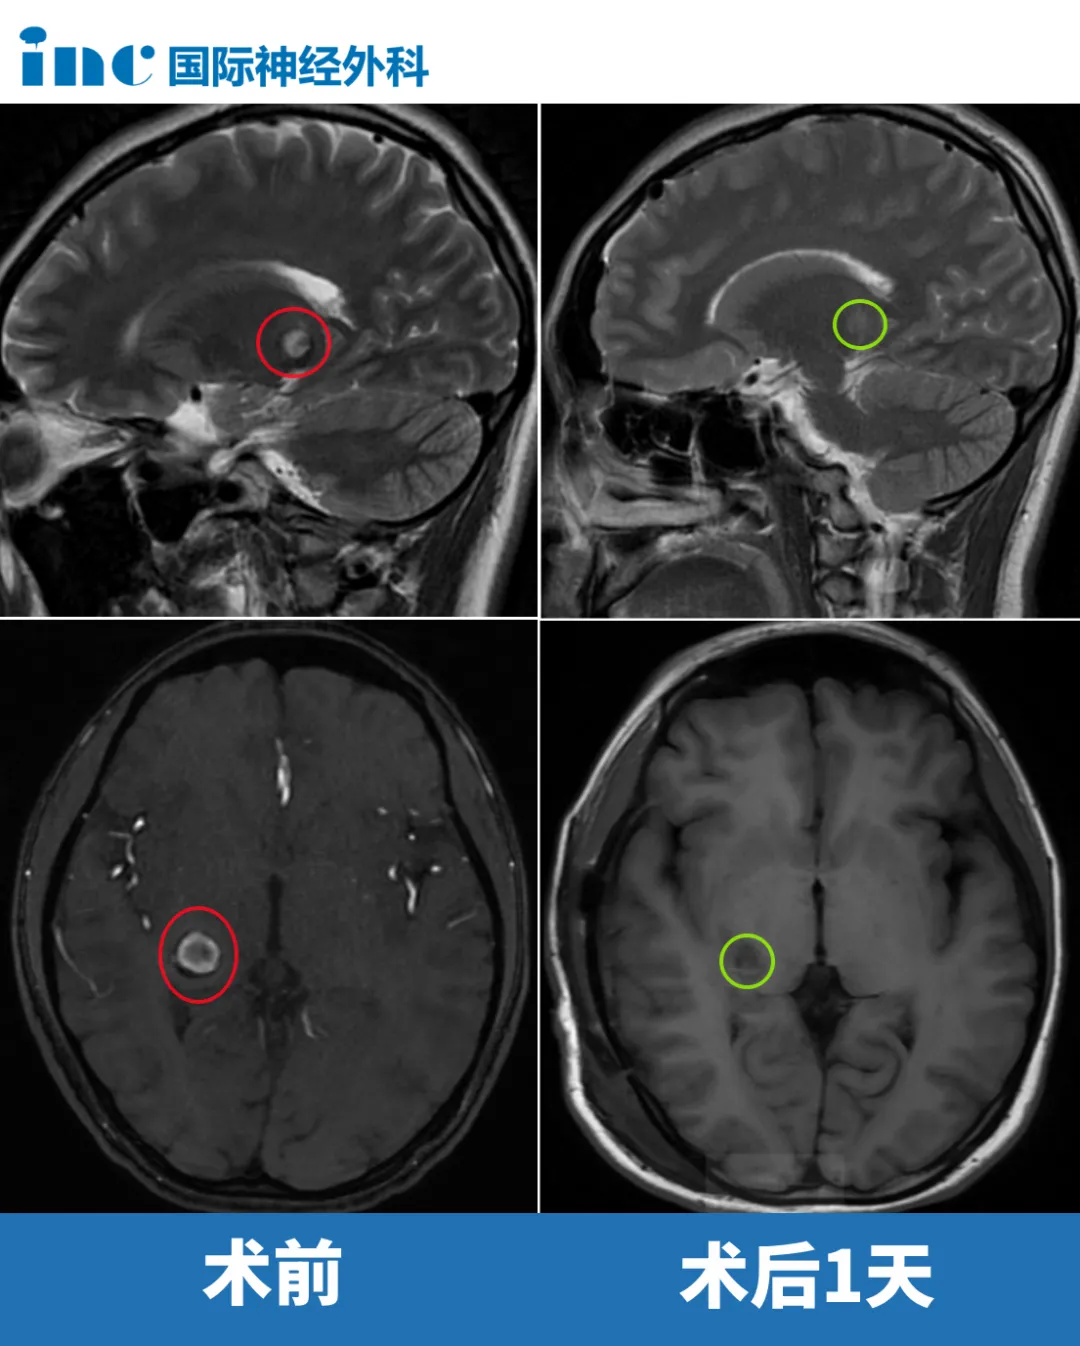

北京時(shí)間2025年10月21日,INC國際神經(jīng)外科醫(yī)生集團(tuán)旗下世界神經(jīng)外科顧問團(tuán)成員巴特朗菲教授,疑難腦瘤示范手術(shù)持續(xù)進(jìn)行中。在蘇州大學(xué)附屬兒童醫(yī)院,“神奇”的巴爺爺又為一名12歲顱咽管瘤男孩濤濤順利手術(shù)。

腫瘤從垂體柄內(nèi)部生長(zhǎng)出來,而垂體柄就像包在外面的一圈薄環(huán),非常細(xì),非常脆弱。垂體柄被腫瘤撐成像氣球一樣,而手術(shù)要開一個(gè)小口,把“氣球”里面的腫瘤取出來,外面這層薄薄的垂體柄還得想辦法保留好。這不僅需要特別精細(xì)的顯微操作,還需要非常特殊的技術(shù)——既要盡量切除腫瘤,又要最大限度地保留這條極其細(xì)小的垂體柄結(jié)構(gòu)。

最終,巴教授主刀,手術(shù)順利完成,垂體柄得到保留,腫瘤切除滿意。

在蘇州大學(xué)附屬第四醫(yī)院,巴教授還為一名26歲的丘腦占位女孩順利手術(shù),獲得了滿意的切除。詳細(xì)內(nèi)容,后續(xù)將深入報(bào)道……